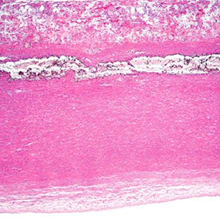

Fibrinous pericarditis

most common form of pericarditis.

In RF & Uraemia

The pericardial cavity contains a mixture of fibrinous exudate with serous fluid.

When two layers of pericardium are pulled apart, 'bread and butter' appearance

(GROSS APPEARANCE)

i. Pericardial surface contains pink fibrinous exudate.

ii. pericardium shows congestion and an acute inflammatory infiltrate composed predominantly of neutrophils.

(MICROSCOPIC APPEARANCE)